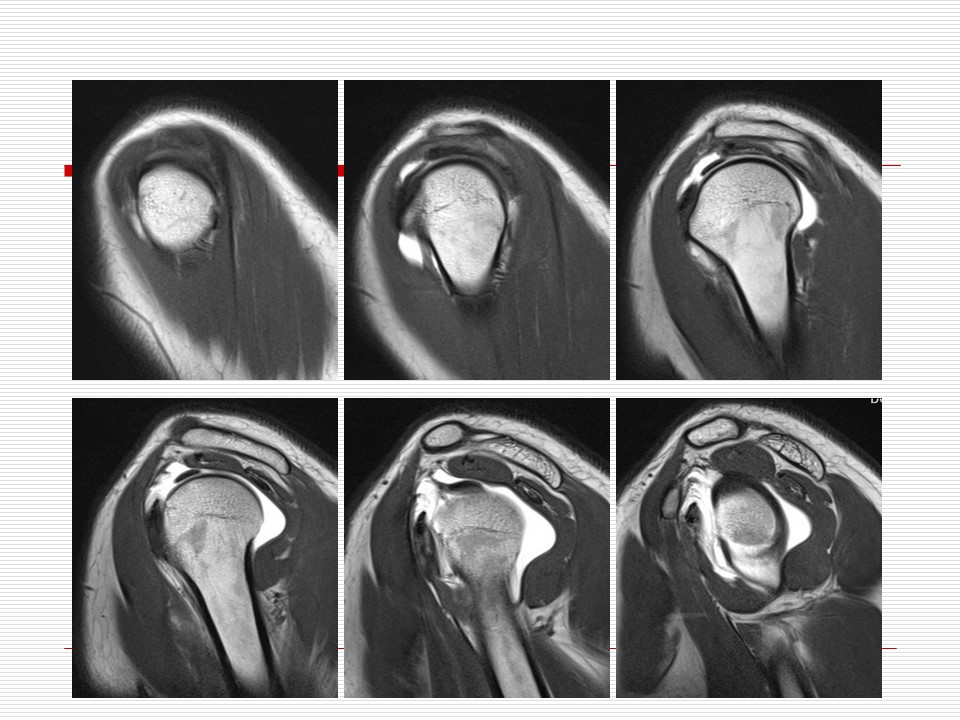

“肩关节解剖及其损伤的MR诊断PPT” 的相关文章